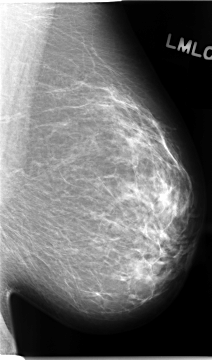

C_0094_1.LEFT_MLO

LEFT_MLO LINES 4680 PIXELS_PER_LINE 2744 BITS_PER_PIXEL 12 RESOLUTION 50 NON_OVERLAY